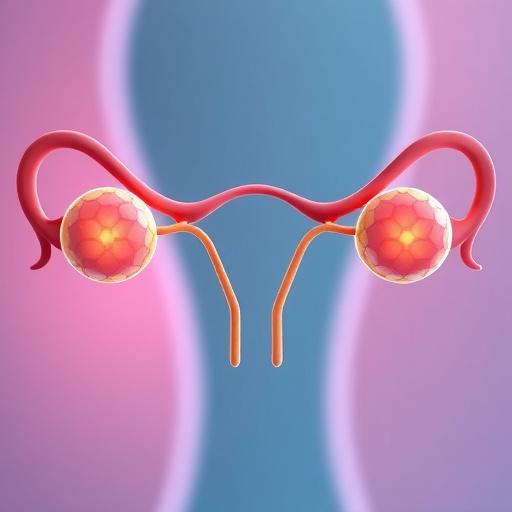

Recent scientific endeavors have illuminated significant advancements in the field of reproductive health, particularly focusing on the establishment and analysis of animal models related to premature ovarian failure (POF). In their recently published work, Wang, Gao, and Li delve into the methodologies that pave the way for a deeper understanding of this complex condition. Premature ovarian failure, characterized by the loss of ovarian function before the age of 40, affects a substantial number of women globally, often resulting in infertility and a subsequent need for sophisticated therapeutic strategies.

Another crucial aspect of establishing effective POF animal models is the evaluation of reproductive outcomes. Beyond merely inducing ovarian failure, it is essential to investigate the subsequent effects on fertility, gamete quality, and overall reproductive health. By incorporating thorough reproductive assessments, researchers can better understand the implications of POF and craft effective interventions aimed at restoring fertility in affected individuals.

The insights garnered from these animal models are pivotal for advancing our grasp of premature ovarian failure. The research by Wang and colleagues provides a strong foundation for future studies, outlining not only the current methodologies employed but also highlighting gaps in knowledge and potential areas for further exploration. As these models continue to evolve, they may unlock new avenues for therapeutic development, offering hope to countless individuals grappling with the consequences of ovarian insufficiency.

In conclusion, the advancements in establishing animal models for premature ovarian failure represent a significant stride in reproductive health research. As researchers build upon the methodologies outlined by Wang, Gao, and Li, the potential for groundbreaking discoveries looms large. This ongoing research not only enhances our understanding of ovarian biology but also endeavors to improve the quality of life for those impacted by POF, thereby underscoring the importance of continued investment in this critical area of study.